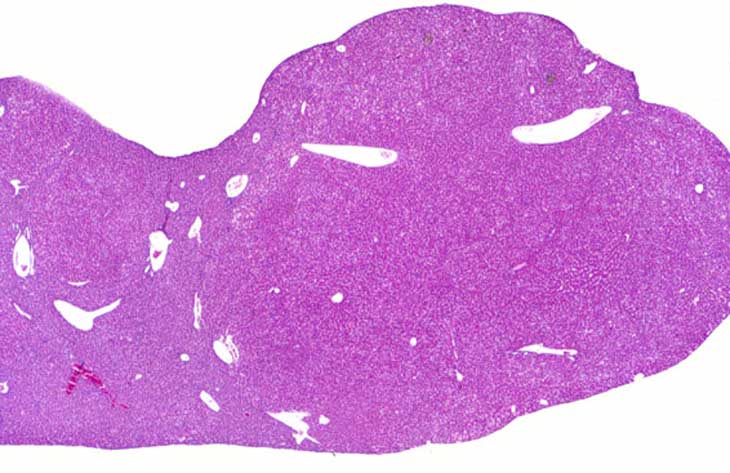

Multiple large and small nodules of regenerating hepatocytes in an Alb-uPA transgenic mouse.